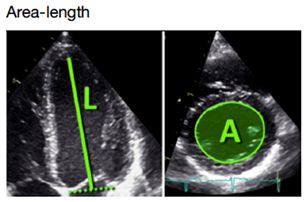

1、部分校正形态改变;

2、心尖缩短常见;

3、显著依赖于几何假设;

4、正常人群数据少。